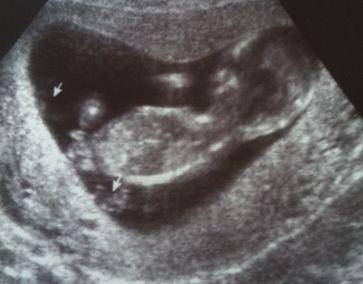

Hier habe ich ein Bild von Dienstag. Wo ich beim Frauenarzt war und Durchfall hatte. Ich habe dann auch ein Bildchen bekommen. Die Pfeile sind die Füße. Als ich mein Mann das Foto mailte, meinte er, es wird ein Junge. Könnt Ihr da was erkennen? Mein Frauenarzt sagte noch nichts.

Hallöchen, erstmal Glückwunsch , tolles Bild ! Ich kann da nicht wirklich was erkennen, da ist so eine Erhebung zwichen den Beinchen, ok, da könnte man mutmaßen, dass es ein Junge wird, habe aber auch mal gelesen, dass beim Mädel, es sich auch erstmal wölb und man bis zur 15.Woche oder so da manchmal keinen Unterschied sieht...Mein Kleines hat sich bis jetzt net so toll hingelegt... ich lass es mir dann erst in der 20.SSW sagen wenn es wirklich deutlich ist ... solange bleibt es spannend bei uns Allen, würde ich sagen... bin gespannt was es dann wirklich bei Dir wird ! LG Mone

Super Bildchen...echt goldig. Also meine FA meinte am vergangenen Dienstag auch, dass die Kinder noch Unisex aussehen und sich die Wölbung bei Jungen nach vorne und bei Mädchen nach innen entwickelt. Im Moment haben sie beide noch was zwischen den Beinchen "Der Wunsch war der Vater des Gedankens" - mein Mann meinte etwas Ähnliches gesehen zu haben.

Es könnte auch die Nabelschnur sein. So wirklich erkennen tue ich nichts. Mal schauen, was es denn wird, in ein paar Wochen erkennt man es eher. Meiner Freundin haben sie damals in der 13. SSW gesagt es wird ein Mädchen und 8 Wochen später war es doch ein Junge geworden und sie war total geknickt. Deshalb ist es auch gut, dass der Arzt nichts gesagt hat. Männer haben gerne ein Wunschdenken. Nach meinem Mann und meinem Sohn bekommen wir auch einen Jungen, die wollen in der Überzahl sein. Zuviel Frauenpower verkraften sie nicht.